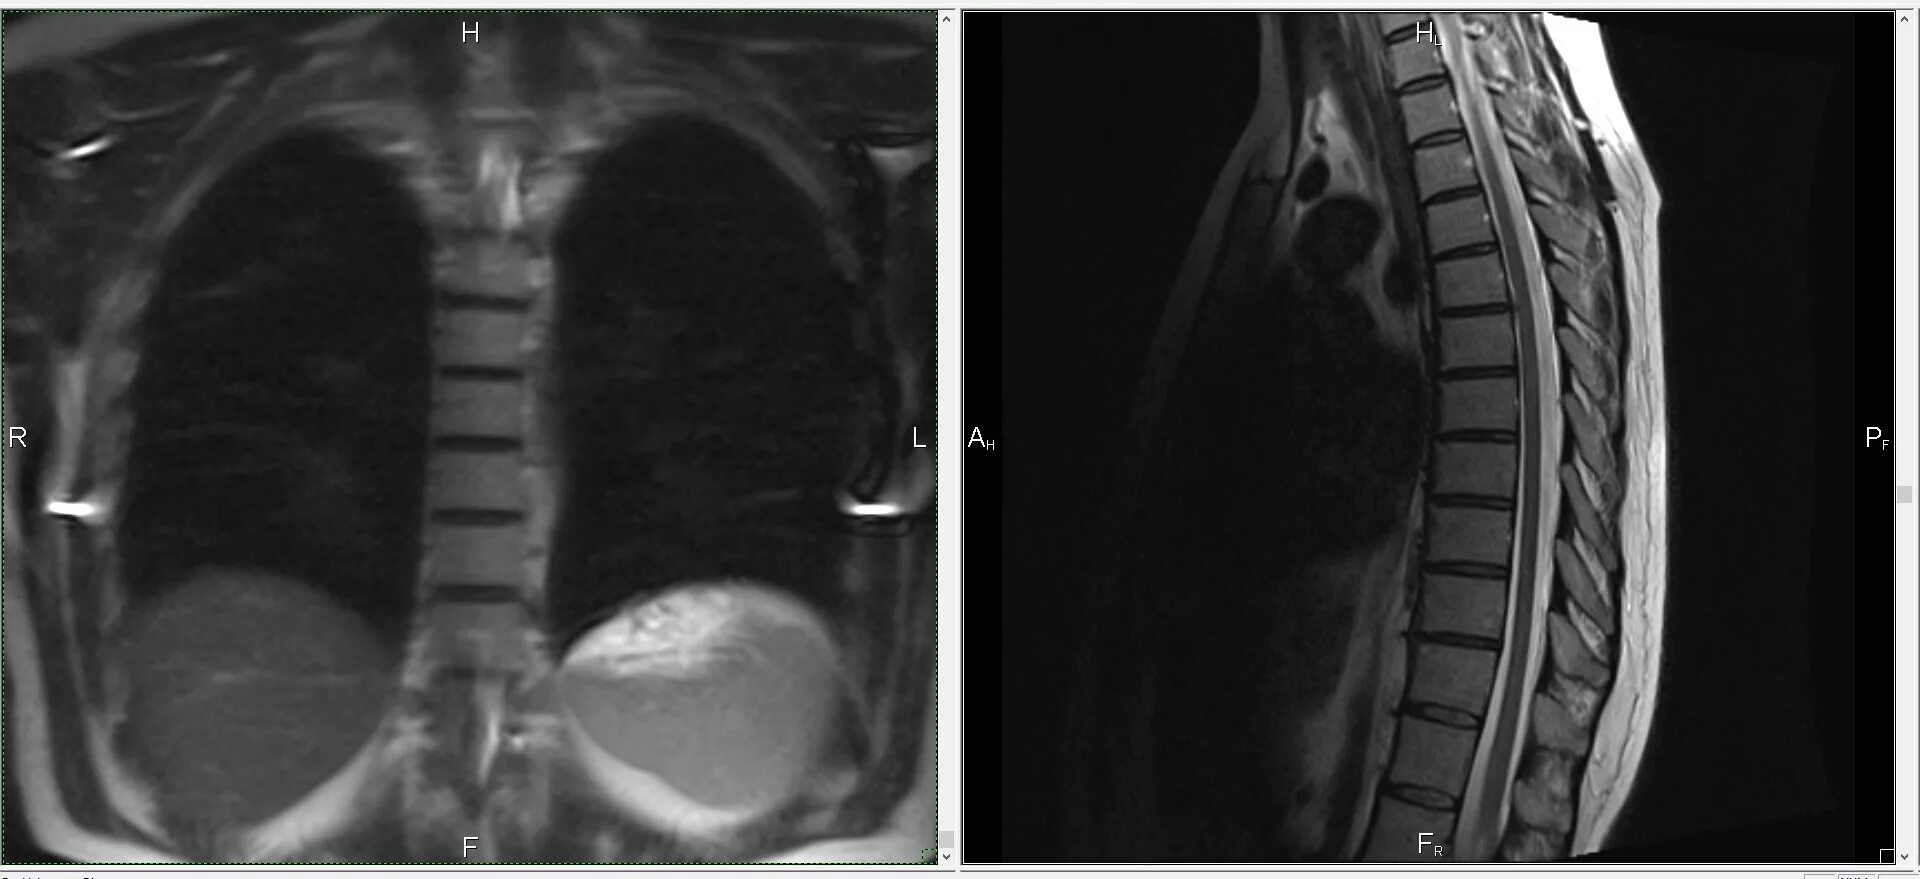

Bypass mrt